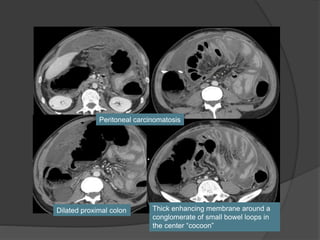

Peritoneal carcinomatosis

Thick enhancing membrane around a

conglomerate of small bowel loops in

the center “cocoon”

Dilated proximal colon

Diagnosed with adenocarcinoma lung 6 months ago

Case 2 Diagnosis: “Cocoon

peritonitis”

•AKA sclerosing

encapsulating peritonitis

•Rare cause of bowel

obstruction due to fibrotic

encapsulation of the bowel

forming a sac or cocoon

•May be idiopathic or

secondary to chronic

peritoneal dialysis, TB,

sarcoidosis, GI malignancy,

fibrogenic foreign material

•Treatment –Surgical

removal of the covering

membrane